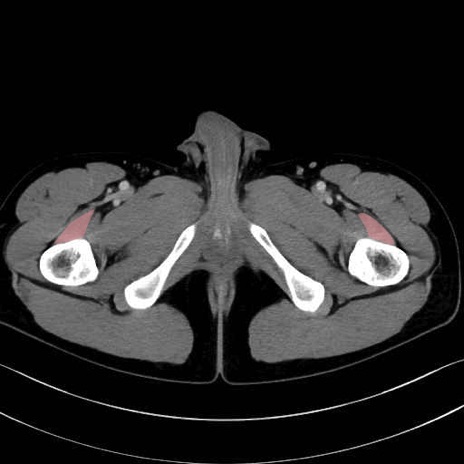

中間広筋 (Vastus intermedius)